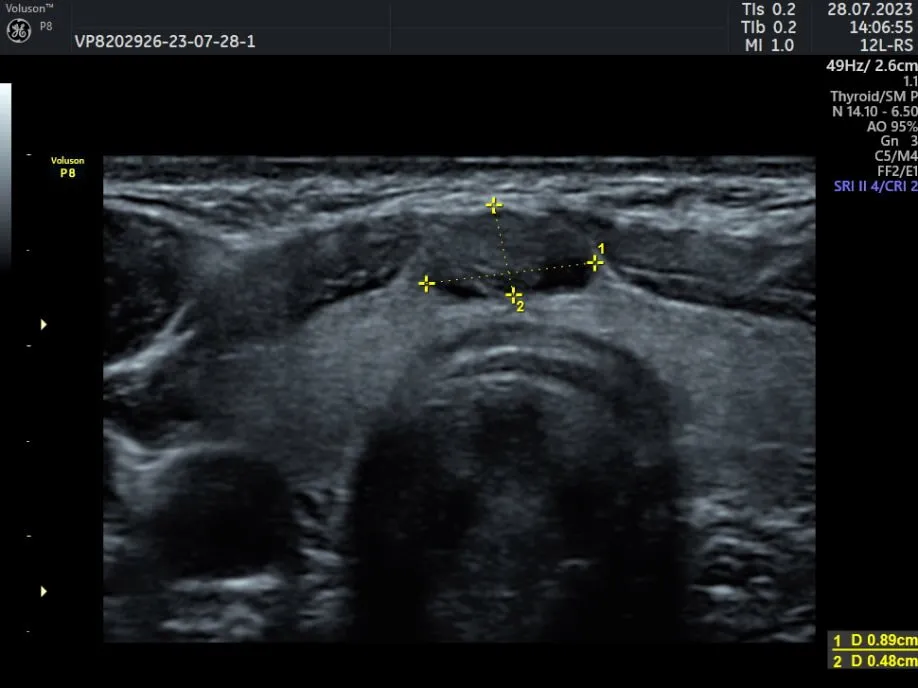

Клинические изображения

- 12L-RS - линейный датчик 4-12 МГц для исследования поверхностно расположенных органов и структур, скелетно-мышечного аппарата, периферических сосудов, педиатри